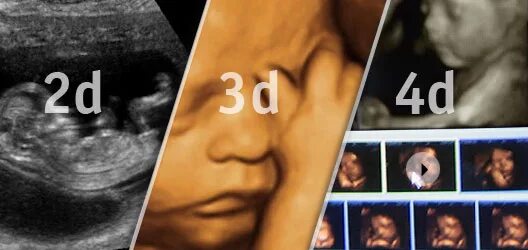

На каком сроке делать 3д